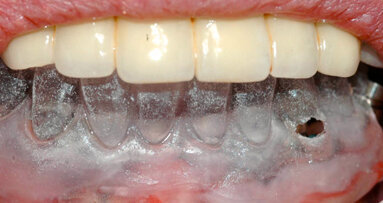

I ricercatori hanno raccontato che il sito trattato è rimasto intatto per 12 mesi, a dimostrazione di un guadagno di 3 mm di attacco clinico e della copertura parziale della radice, senza segni di infiammazione cronica o deiscenza. Tuttavia, 13 mesi dopo la terapia, la struttura si è esposta.

Anche se questa prima applicazione di uno scaffold stampato in 3D non ha avuto successo, nel lungo periodo, i ricercatori hanno concluso che ulteriori ricerche in merito all’applicazione di tale tecnologia e al miglioramento del riassorbimento potrebbero portare a un nuovo e più personalizzato approccio clinico alla medicina rigenerativa orale.